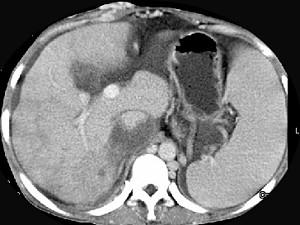

问题 女性,26岁,腹胀不适7月,腹软,肝右肋缘下1cm,影像检查如图,可能的诊断为 ( )

选项 A、布加综合征 B、脂肪肝 C、原发性肝癌 D、肝硬化腹水 E、肝血管瘤

答案 A